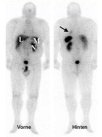

Einen weiteren Eckpfeiler für die Lokalisationsdiagnostik stellt die Somatostatinrezeptor-szintigraphie (Octreotid-Szintigraphie) dar. Die Nuklearmedizin bietet derzeit verschiedene Tracer an, die sich bezüglich der Eigenschaften der Rezeptorliganden und der Markierungsnuklide unterscheiden. Mit dem 111In-markierten Octreotid liegen langjährige Erfahrungen vor. Die positive Darstellung der Tumoren ist eine unabdingbare Voraussetzung für die Indikationsstellung zur Therapie mit radioaktiven Somatostatinrezeptoranaloga.